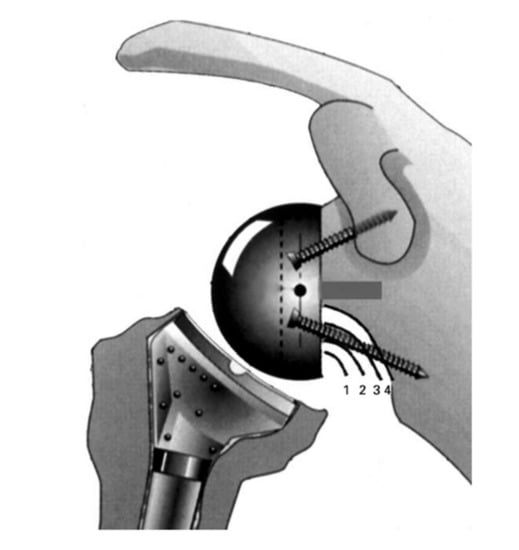

- (1)

- The computed sphere that best fits the 3D model of the glenoid concavity is displayed with the glenoid best fit sphere radius (GBFSR), a marker of the glenohumeral size (observed range: 25–45 mm). Patients with GBFS of less than 30 mm are at higher risk of overstuffing.

- (2)

- Lateralization (variation 0 to +10 mm): The surgeon should be cautious with lateralization beyond +5–10 mm depending on the amount of loss of medial bone stock. Excessive superior migration (vertically decentered) but, more importantly, posterior (e.g., B2 glenoid) and anterior subluxation are signs that there will be increased tension when attempting to reduce the RSA.

- (3)

- Distalization (variation: 20 to +40 mm) depends on the amount of cranial humeral head migration. The surgeon should be cautious with distalization beyond 35–40 mm.